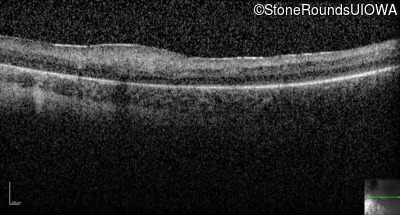

Optical Coherence Tomography - Left -

Light Perception

Exemplar / OCT Stack